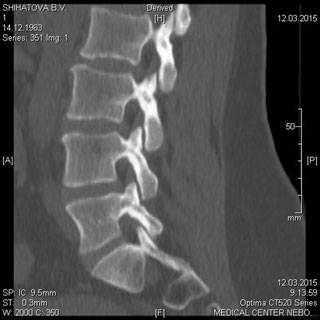

МСКТ позвоночника и спинного мозга.

Метод МСКТ очень ценен для выявления дегенеративно-дистрофических изменений, диагностируются грыжи дисков и элементы, суживающие позвоночный канал. МРТ превосходит визуализацию спинного мозга, содержимое дурального мешка, возможность увидеть другие уровни. Однако для пациентов с типичным течением болезни локализацией симптомов на одном уровне с одной стороны МСКТ обычно достаточна для постановки диагноза.

Показания:

- подозрение на опухолевое, метастатическое поражение с деструкцией

- травматическое поражение

- подозрение на грыжу диска (с обязательным указанием сегмента поражения) при невозможности проведения МРТ

- воспалительные процессы (специфические и неспецифические) с деструкцией костных структур

Подготовка: не требуется. Предварительное рекомендуемое обследование: заключение невролога